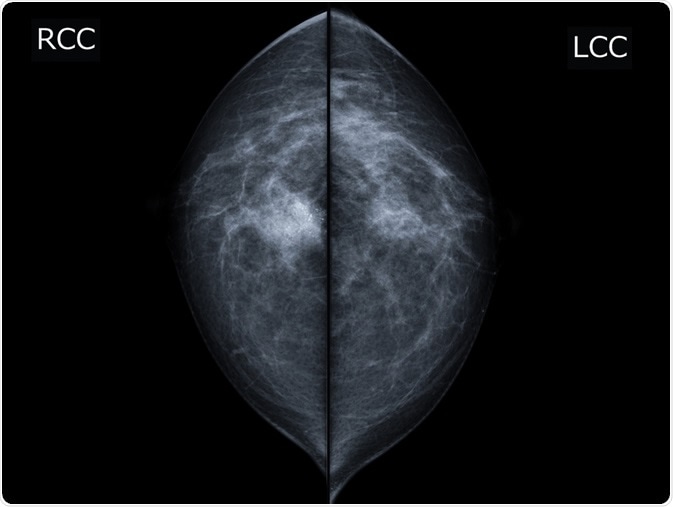

X-ray mammogram image of breast with cancer. - breast cancer of right breast. Image Credit: MossStudio / Shutterstock